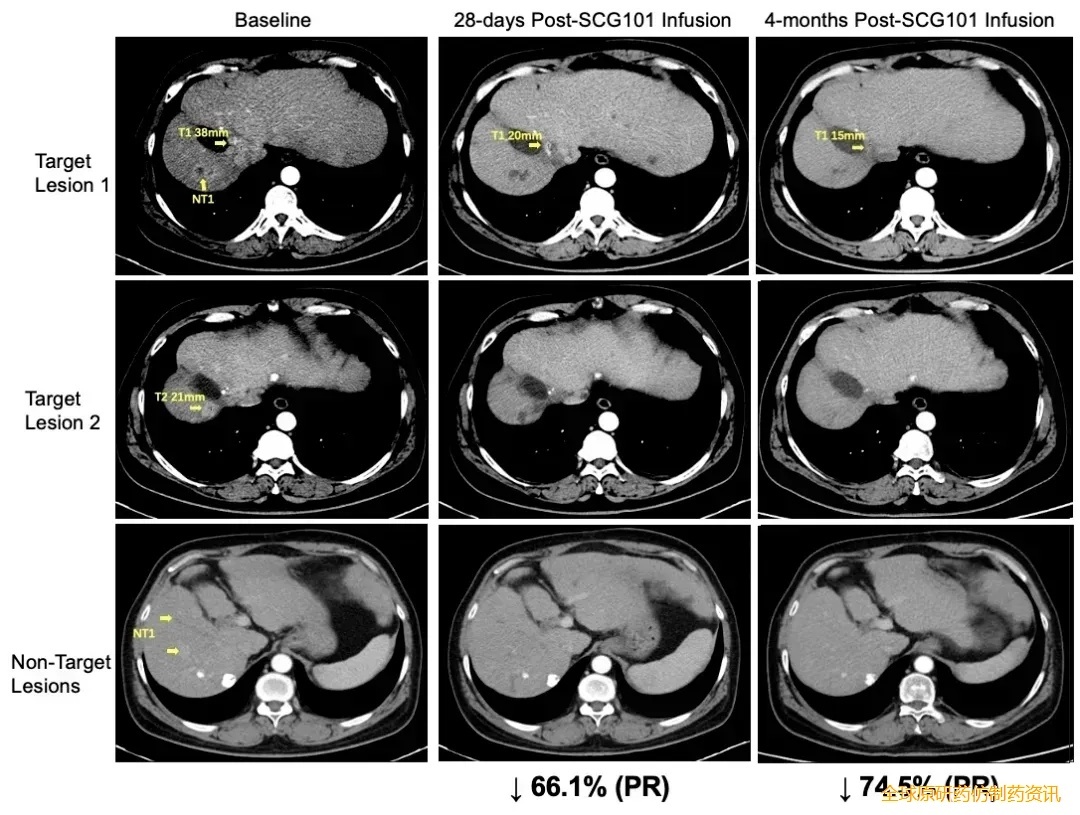

SCG101还曾在2023年公布过突破性案例:1例患者单剂治疗后,靶病灶第28天缩小66%达部分缓解(PR),第4个月进一步缩小至74.5%且1处病灶完全消失(详见下面影像图),无进展生存期超6.9个月(未联合其他治疗);HBV病毒同步清零——肝脏免疫组化显示HBsAg阳性肝细胞100%清除,血清HBsAg从557.96IU/mL骤降至第7天1.3IU/mL、第28天0.08IU/mL(详见下图)。

▲图源“SCG”,版权归原作者所有,如无意中侵犯了知识产权,请联系我们删除